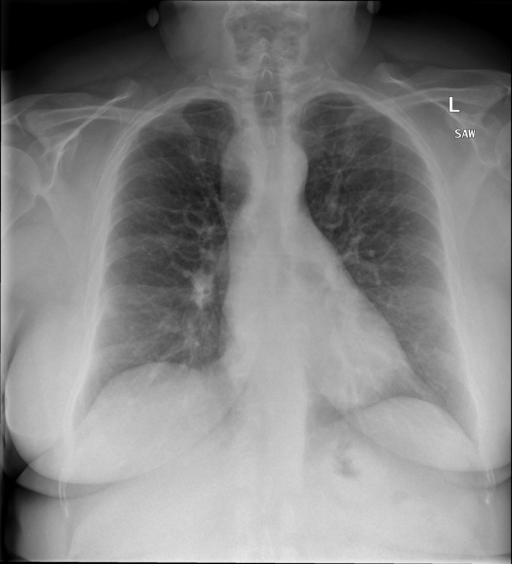

## 本文贡献 ![](./assets/images/xrayglm.png) - 借助ChatGPT以及公开的数据集,我们构造了一个`X光影像-诊断报告`对的医学多模态数据集; - 我们将构建的中文胸部X光片诊断数据集在[VisualGLM-6B](https://github.com/THUDM/VisualGLM-6B)进行微调训练,并开放了部分训练权重用于学术研究; ## 数据集 - [MIMIC-CXR](https://physionet.org/content/mimic-cxr-jpg/2.0.0/)是一个公开可用的胸部X光片数据集,包括377,110张图像和227,827个相关报告。 - [OpenI](https://openi.nlm.nih.gov/faq#collection)是一个来自印第安纳大学医院的胸部X光片数据集,包括6,459张图像和3,955个报告。 在上述工作中,报告信息都为非结构化的,不利于科学研究。为了生成合理的医学报告,我们对两个数据集进行了预处理,并最终得到了可以用于训练的**英文报告**。除此之外,为了更好的支持中文社区发展,借助ChatGPT的能力,我们将英文报告进行了中文翻译,并最终形成了可用于训练的数据集。 |数据集|数量|下载链接| |:-|:-|:-| |MIMIC-CXR-zh|-|-| |OpenI-zh|6,423|[诊疗报告(英文)](./data/openi-en.json)、[诊疗报告(中文)](./data/Xray/openi-zh.json) 、[X光影像](https://pan.baidu.com/s/13GBsDMKf6xBZBSHpoWH_EA?pwd=k9sh)| ## 快速上手 1. 安装环境 ```bash # 安装依赖 pip install -r requirements.txt # 国内换源安装依赖 pip install -i https://mirrors.aliyun.com/pypi/simple/ -r requirements.txt ``` 此时默认会安装`deepspeed`库(支持`sat`库训练),此库对于模型推理并非必要,同时部分`Windows`环境安装此库时会遇到问题。 如果想绕过`deepspeed`安装,我们可以将命令改为: ```bash # 安装依赖 pip install -i https://mirrors.aliyun.com/pypi/simple/ -r requirements_wo_ds.txt # 安装SwissArmyTransformer pip install -i https://mirrors.aliyun.com/pypi/simple/ --no-deps "SwissArmyTransformer>=0.3.6" ``` 2. 模型推理 |模型权重|下载链接| |:-|:-| |checkpoints-XrayGLM-300|-| |checkpoints-XrayGLM-3000|-| CLI推理: ```python python cli_demo.py --from_pretrained checkpoints/checkpoints-XrayGLM-3000 --prompt_zh '详细描述这张胸部X光片的诊断结果' ``` 更多[参数](https://github.com/WangRongsheng/XrayGLM/blob/main/cli_demo.py#L16) ## 效果展示 影像诊断: |X光影像|诊疗报告(医生)|XrayGLM| |:-|:-|:-| |![](./data/Xray/2_1.png)|根据X射线图像,心脏大小正常,肺部看起来很清晰。已经排除了肺炎、积液、水肿、气胸、腺病、结节或肿块的存在。该发现表明一切正常。换句话说,总体印象是胸部正常。|X光片显示,心脏大小正常。肺部没有气胸或胸腔积液的证据。骨骼结构看起来没有任何异常。总的来说,X光片表明没有发现急性心肺疾病的迹象。| |![](./data/Xray/2882_1.png)|X光图片显示没有扭曲的区域、可疑的骨质不透明度或胸腺积液。心脏大小轻微增大,但非常稳定。此外,没有气胸的证据,肺野也正常。总体来说,X光片显示没有急性心脏异常,但要注意轻微的心脏扩大。|X光片显示,心脏大小正常。肺部和纵隔轮廓清晰,没有气胸或胸腔积液的证据。骨骼结构完整,没有任何急性异常。| |![](./data/Xray/2577_1.png)|心影形态在正常范围内。没有急性骨质异常。有可能出现没有明显的吸水或肺实质状况的线索。没有大面积积液或气胸。有可能怀疑其有误吸或肺实质问题。为了确诊和治疗,可能需要进行适当的影像学随访。|心脏大小正常,肺部和纵隔轮廓清晰。没有急性异常或活动受限的证据。没有任何明显的气胸、胸腔积液或肺不张的迹象。此外,也没有发现任何局灶性骨质异常或其他急性疾病。| 多轮对话: |X光影像|诊疗报告(医生)| |:-|:-| |![](./data/Xray/861_1.png)|右侧主动脉突出观察到。心脏大小正常。胸部未发现明显的肺气肿、胸膜积液或可疑的肺部病变。报告指出已知右侧主动脉情况正常。| ```bash >> X光影像路径:./data/Xray/861_1.png >> 用户:这是一张什么图? >> XrayGLM:这张图片显示的是一张肺部检查的X光片。 >> 用户:请描述这张胸部X光片的诊断结果 >> XrayGLM:心脏大小正常,肺部清晰。没有急性心肺疾病的证据。 >> 用户:是否存在肺气肿? >> XrayGLM:没有肺气肿。心脏大小正常,肺部清晰。没有发现急性心肺疾病的证据。 >> 用户:平时饮食该注意什么? >> XrayGLM:饮食应该健康,均衡。建议增加蛋白质的摄入量,因为蛋白质有助于维持肌肉和骨骼的健康。多食用蔬菜、水果、全谷物以及健康的脂肪来源如橄榄油、鱼类等可以帮助获得足够的维生素和矿物质。此外,避免过度饮酒或吸烟,这些习惯可能会对心脏健康产生负面影响。 ``` ## 未来展望 1. 模型的能力更多来源于数据的支持,`OpenI-zh`作为微调数据集,其数据量足以支持研究,在更广泛的任务和性能表现上,我们认为**在大规模数据集上预训练并在高质量少量数据集上微调是一种可行的方案**; 2. 普遍意义的理解上,视觉多模态模型=视觉模型+语言模型。除了需要关注视觉模型信息与语言模型输出的搭配外,还需要**额外关注到语言模型的加强,在人机的对话中,尤其是医疗语言模型的问答上,除了专业的医疗问题回答,带有人文情怀的有温度的回答更应该是我们追寻的目标**。 ## 项目致谢 1. [VisualGLM-6B](https://github.com/THUDM/VisualGLM-6B)为我们提供了基础的代码参考和实现; 2. [MiniGPT-4](https://github.com/Vision-CAIR/MiniGPT-4)为我们这个项目提供了研发思路; 3. ChatGPT生成了高质量的中文版X光检查报告以支持XrayGLM训练; 4. [gpt_academic](https://github.com/binary-husky/gpt_academic)为文档翻译提供了多线程加速; 5. [MedCLIP](https://github.com/RyanWangZf/MedCLIP) 、[BLIP2](https://huggingface.co/docs/transformers/main/model_doc/blip-2) 、[XrayGPT](https://github.com/mbzuai-oryx/XrayGPT) 等工作也有重大的参考意义; ![](./assets/images/mpu.png) 这项工作由[澳门理工大学应用科学学院](https://www.mpu.edu.mo/esca/zh/index.php)硕士生[王荣胜](https://github.com/WangRongsheng) 、[段耀菲](https://github.com/IsBaSO4) 、[李俊蓉](https://github.com/lijunrong0815)完成,指导老师为檀韬副教授、[彭祥佑](http://www.patrickpang.net/)老师。 *特别鸣谢:[USTC-PhD Yongle Luo](https://github.com/kaixindelele) 提供了有3000美金的OpenAI账号,帮助我们完成大量的X光报告翻译工作 ## 免责声明 本项目相关资源仅供学术研究之用,严禁用于商业用途。使用涉及第三方代码的部分时,请严格遵循相应的开源协议。模型生成的内容受模型计算、随机性和量化精度损失等因素影响,本项目无法对其准确性作出保证。即使本项目模型输出符合医学事实,也不能被用作实际医学诊断的依据。对于模型输出的任何内容,本项目不承担任何法律责任,亦不对因使用相关资源和输出结果而可能产生的任何损失承担责任。 ## 项目引用 如果你使用了本项目的模型,数据或者代码,请声明引用: ```bash @misc{wang2023XrayGLM, title={XrayGLM: The first Chinese Medical Multimodal Model that Chest Radiographs Summarization}, author={Rongsheng Wang, Yaofei Duan, Junrong Li, Patrick Pang and Tao Tan}, year={2023}, publisher = {GitHub}, journal = {GitHub repository}, howpublished = {\url{https://github.com/WangRongsheng/XrayGLM}}, } ``` ## 使用许可 此存储库遵循[CC BY-NC-SA](https://creativecommons.org/licenses/by-nc-sa/4.0/) ,请参阅许可条款。